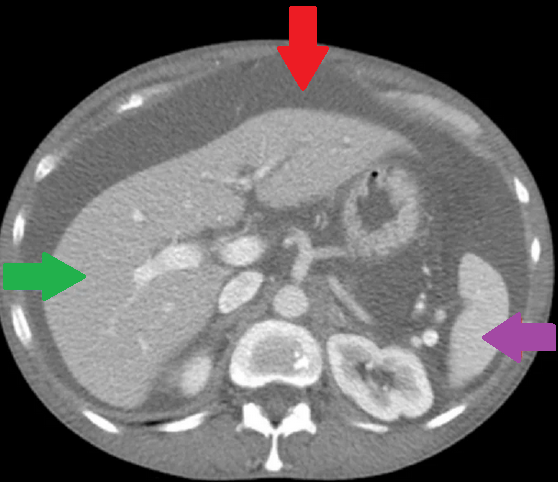

Ένας 46χρονος ασθενής , με μακροχρόνιο πρόβλημα γαστρο-οισοφαγικής παλινδρόμησης , ανθεκτικής στην συντηρητική θεραπεία , υποβλήθηκε σε λαπαροσκοπική θολοπτύχωση κατά Nissen , σε άλλο νοσοκομείο της πόλης μας . Κατά δήλωση του , η όλη διαδικασία εξελίχθηκε ομαλά και έλαβε εξιτήριο 2 ημέρες αργότερα . Μετά την παρέλευση 20ημέρου , ο ασθενής προσήλθε στο Τμήμα Επειγόντων Περιστατικών του Νοσοκομείου μας , βαριά αφυδατωμένος με κλινικά και εργαστηριακά ευρήματα νεφρικής ανεπάρκειας προνεφρικής αιτιολογίας . Από την λήψη του ιστορικού , προέκυψε πως άρχισε να βήχει επίμονα και να δυσκολεύεται στην αναπνοή τις τελευταίες 4 ημέρες. Η κλινική εξέταση ανέδειξε μεγάλη διάταση της κοιλίας συνοδευόμενη από διάχυτη ευαισθησία ενώ η αξονική τομογραφία θώρακος και κοιλίας , αποκάλυψε την παρουσία πλευριτικών συλλογών αμφοτερόπλευρα και ασκιτικού υγρού στην περιτοναική κοιλότητα . Εικόνα 1 . Αξονική Τομογραφία θώρακος – Αμφοτερόπλευρη παρουσία πλευριτικών συλλογών . ( Αρχείο κος Β . Πενόπουλος ) . Εικόνα 2 . Αξονική Τομογραφία κοιλίας . Κόκκινο βέλος – Ασκίτης . Μώβ βέλος – Σπλήνας . Πράσινο βέλος – Ήπαρ . ( Αρχείο κος Β . Πενόπουλος ) . Παρακεντήσαμε τόσο τις πλευριτικές συλλογές , όσο και τον ασκίτη και ζητήσαμε βιοχημικό έλεγχο , ο οποίος ανέδειξε υψηλά επίπεδα λευκώματος και τριγλυκεριδίων σε όλα τα δείγματα ( 154 mg/dL ) . Με το εύρημα αυτό , θέσαμε την διάγνωση του αμφοτερόπλευρου χυλοθώρακα και του χυλώδους ασκίτη . Κατόπιν τούτου , ο ασθενής διακομίστηκε στην Θωρακο-χειρουργική Κλινική , όπου τοποθετήθηκαν θωρακο-σωλήνες αμφοτερόπλευρα και παροχετεύτηκαν 1.2 λίτρα χυλώδους περιεχομένου από αμφότερες τις θωρακικές κοιλότητες . Η σίτιση από του στόματος διεκόπη και ο ασθενής έλαβε ενδοφλεβίως ολική παρεντερική διατροφή και σωματοστατίνη . Παρά την συντηρητική αγωγή , η διαρροή του χυλού συνεχίστηκε , οπότε λόγω αδυναμίας εντοπισμού του σημείου του τραυματισμού , αποφασίστηκε και εκτελέστηκε απολίνωση του θωρακικού πόρου , μεταξύ της αορτής και της αζύγου φλεβός στο επίπεδο μεταξύ 8ης και 9ης πλευράς δεξιά . Δυστυχώς , παρά την επιτυχή επέμβαση , η διαρροή συνεχίστηκε και ζητήθηκε εκ νέου η συμβολή μας στην επίλυση του προβλήματος . Μετά την μεταφορά στην κλινική μας , αποφασίσαμε και εκτελέσαμε διποδική λεμφαγγειογραφία , η οποία ανέδειξε εκτεταμένη διαρροή από τον θωρακικό πόρο στο ύψος του Τ9 και συγκέντρωση του στο αριστερό υποχόνδριο . Εικόνα 3 . Λεμφαγγειογραφία . Κόκκινο βέλος – Σημείο τραυματισμού . (Αρχείο κος Β . Πενόπουλος) . Με την συνδρομή του επεμβατικού ακτινολόγου , επετεύχθη ο καθετηριασμός του θωρακικού πόρου , κάτωθεν του σημείου της διαρροής και ο εμβολισμός με κόλλα N-butyl- cyanoacrylate . Εικόνα 4 . Καθετηριασμός θωρακικού πόρου και έγχυση κόλλας . Η παρέμβαση ήταν απολύτως επιτυχής και είχε σαν αποτέλεσμα την σταδιακή μείωση των εξερχόμενων ποσοτήτων από τις θωρακικές παροχετεύσεις όσο και της περιμέτρου της κοιλίας . Μετά την πλήρη αποστράγγιση τους , οι θωρακοσωλήνες αφαιρέθηκαν και ο ασθενής ελεύθερος συμπτωμάτων , επανήλθε στην σίτιση από του στόματος . Εξήλθε του Νοσοκομείου , λίγες ημέρες αργότερα και μετά παρέλευση 6μήνου , ήταν ελεύθερος συμπτωμάτων , σιτίζονταν ελεύθερα από του στόματος , είχε πετύχει σημαντική απώλεια βάρους , η περίμετρος της κοιλίας του είχε επανέλθει στα φυσιολογικά επίπεδα και δεν υπήρχαν ευρήματα που να συνηγορούν στην υποτροπή του χυλώδους ασκίτη .